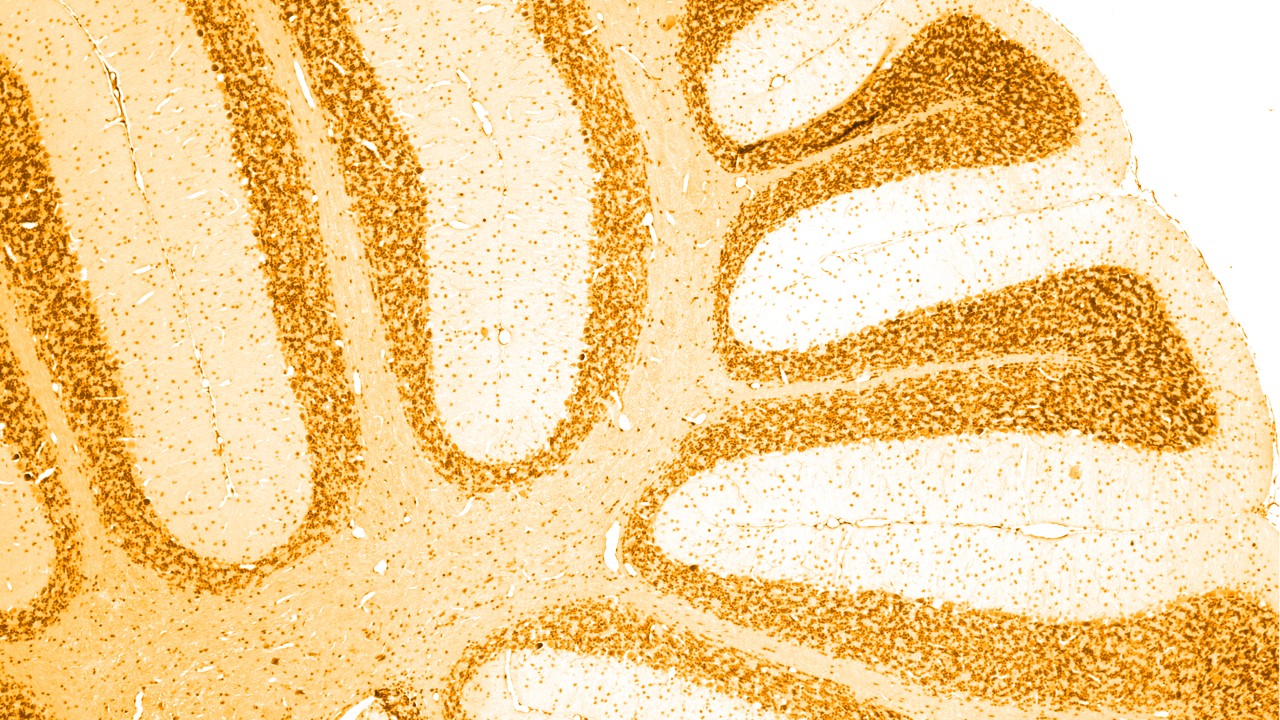

Neurologiska tillstånd är sjukdomar i det centrala och det perifera nervsystemet. Det vill säga i hjärnan, ryggmärgen, nerverna och musklerna som styr och samordnar kroppsfunktioner.